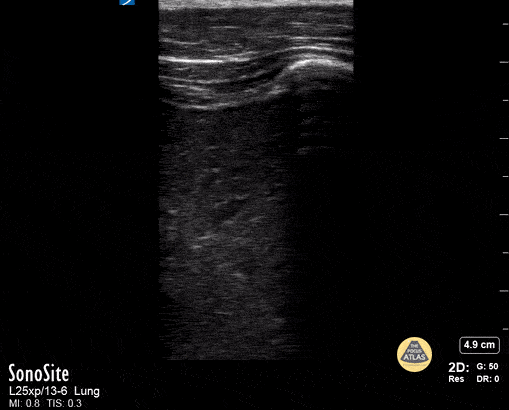

Peds-Lung - Lung Consolidation

Lung consolidation in a child with fever and cough; faint dynamic air bronchogram seen Contributor: Peter Gutierrez, MD, FAAP, Emory University School of Medicine/Children's Healthcare of Atlanta, @pocuspete